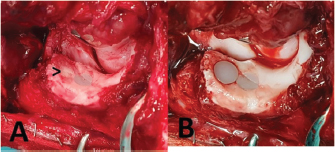

Septic arthritis and implant loosening occurred in one case. This dog initially received two ulnar implants due to extensive ulnar cartilage erosion and was re-presented 6 weeks after the surgery with severe lameness and pain. No signs of implant loosening or migration were apparent on radiographs. Diagnosis of septic arthritis was based on synovial cytological analysis and later a highly sensitive Staphylococcus intermedius genus confirmed by microbial culture. Second look arthroscopy revealed loosening of the cranial UImpl, which could be easily manipulated with a hook probe. The loose UImpl was removed arthroscopically and the joint was thoroughly lavaged. The second UImpl was left in place as it appeared completely stable and well-integrated. The same applied to the HImpl. Systemic antibiotic treatment with Amoxicillin-Clavulanate (Synulox®, Zoetis, Germany) was initiated and continued for 4 weeks. Cytological cell count dropped to values below 1000 cells/μL with three negative consecutive joint taps. Within 8 weeks after revision, surgery limb function improved significantly. Third-look arthroscopy was performed 3 months after second-look and fibrocartilage infill of the former implant bed was noted. Both remaining implants appeared stable and well-integrated. However, the HImpl had grinded along its axial border into the MCP at a depth of about 0.5 mm (Fig. 8A). That groove extended from the tip of the MCP over the retained caudal UImpl, 3 mm caudal to it. The joint was accessed via the caudo-medial approach and the implant bed of the previously explanted implant was over reamed with the large sized reamer (previously a medium UImpl) and a large UImpl was implanted (Fig. 8B). Using a high-speed burr, the groove at the MCP was leveled out to achieve a smooth joint surface. No further treatment was performed. At the last follow-up examination 4 months after revision surgery and 10 months after initial surgery, respectively, lameness improved significantly and the dog achieved an acceptable outcome with a LOAD score of 23.

Fig. 8. Revision surgery in a case with septic arthritis and implant loosening 8 weeks after removal of the cranial ulnar implant. (A) Groove-like chondral and subchondral defect with signs of wear of the remaining implant, arrow—fibrocartilage infill of the former implant bed and (B) Over reamed bed of the initial implant with an implanted large-sized ulnar implant.